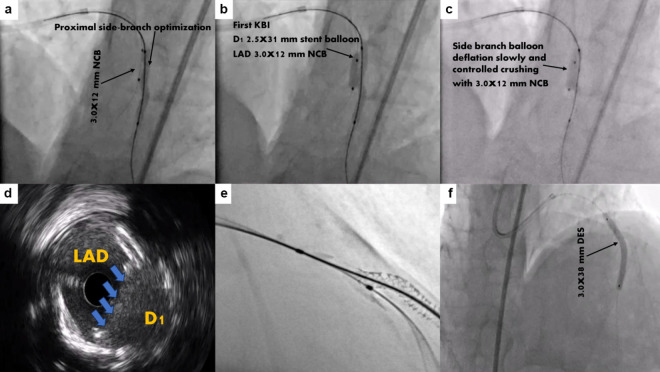

A Novel Modified Mini-Crush Technique for Complex Coronary Bifurcation Lesions: Controlled Balloon-Crush